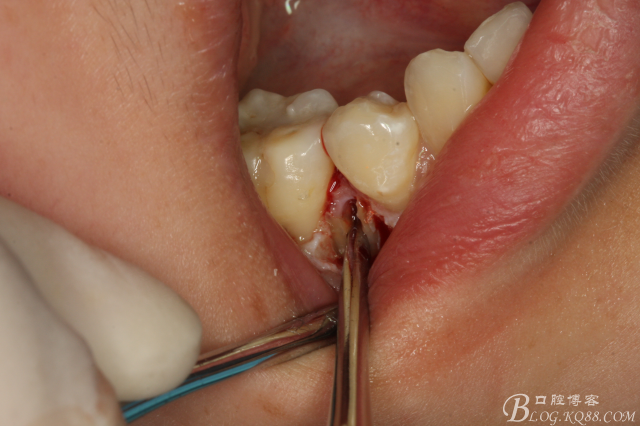

圖5.局部麻醉下、在44近中做垂直小切口,切口不要超過膜齦聯(lián)合。

圖6.齦溝內(nèi)水平切口

圖7.翻小瓣。暴露45牙根斷面